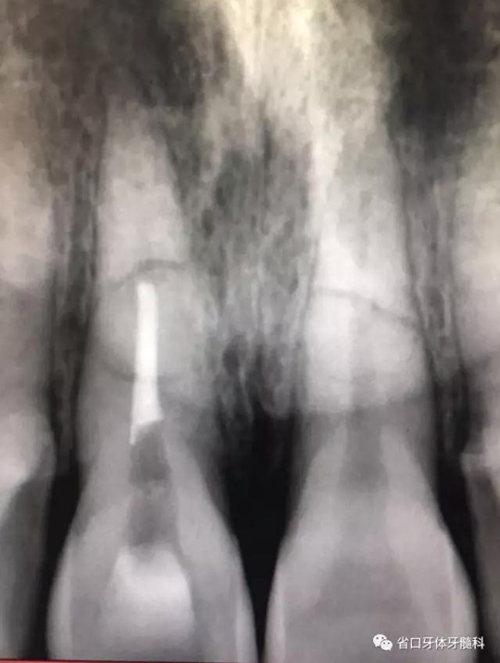

CBCT:11、21頸部以下均見一完全性折裂線,兩牙折裂線均位于頜骨內(nèi)且斷端移位不明顯,相應唇側(cè)骨板亦見斷裂且輕度移位。

圖3:11術前CT

圖4:21術前